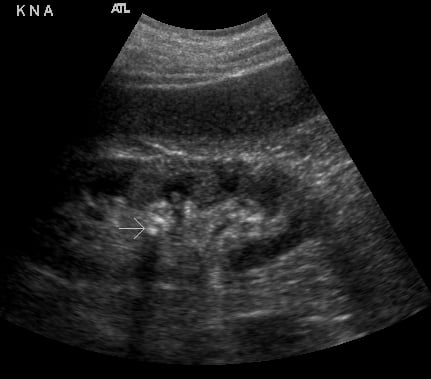

- Figure 2. Moderate hydronephrosis demonstrating location of ureter (surrounded by arrows) exiting renal pelvis

- Figures 5 and 6. Renal stones (arrows) with shadowing

- Stones at the ureteropelvic junction - look for a bright object that casts a shadow at the hilum as the renal pelvis narrows to form the ureter.

- Figure 7. Stone in the mid-ureter in setting of hydroureter (Courtesy of Dasia Esener, MD)